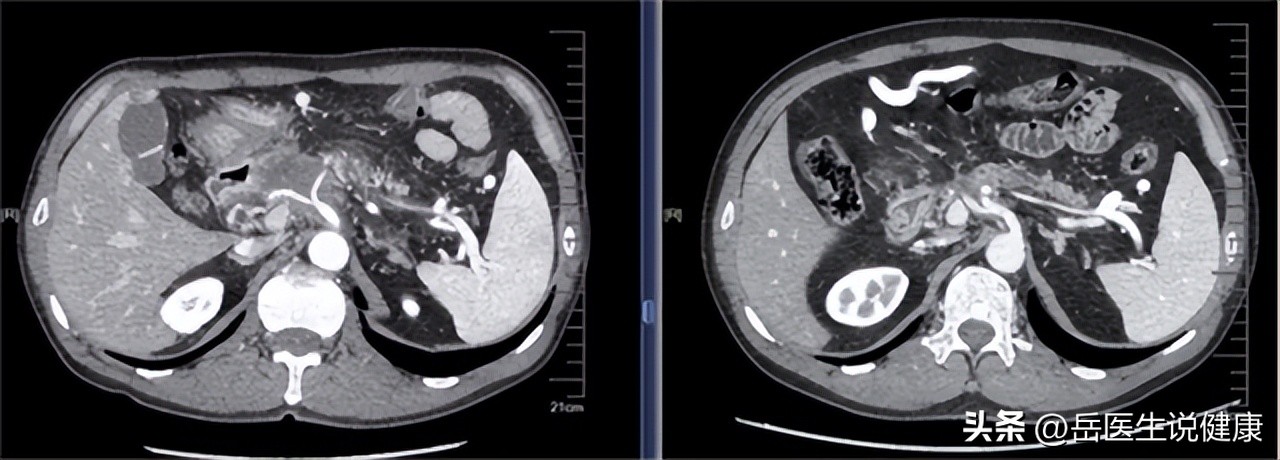

急诊医生接到王先生后进行查体,结果显示:腹部隆起,上腹部疼痛剧烈,神志不清,体温升高,询问原因得知是饮酒过度,考虑急性胰腺炎,安排腹部CT扫描。

实验室检查结果显示:血尿淀粉酶增高。CT显示胰腺轮廓扩大呈现为低密度不规则形状,弥漫性肥厚表现明显,诊断为急性胰腺炎。